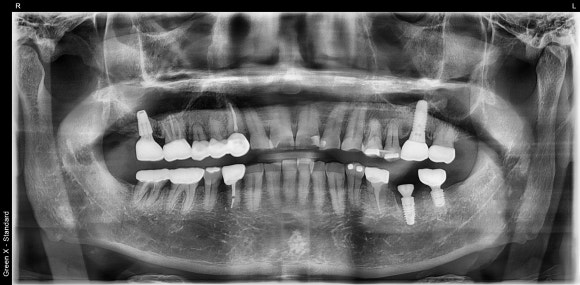

20250217

최종 파노라마 사진입니다.

- 워랜텍 임플란트를 사용했습니다. 출시 이후로 거의 변하지 않은 안정적인 디자인, 믿음직스러운 임상결과로 저는 워랜텍을 선호합니다.